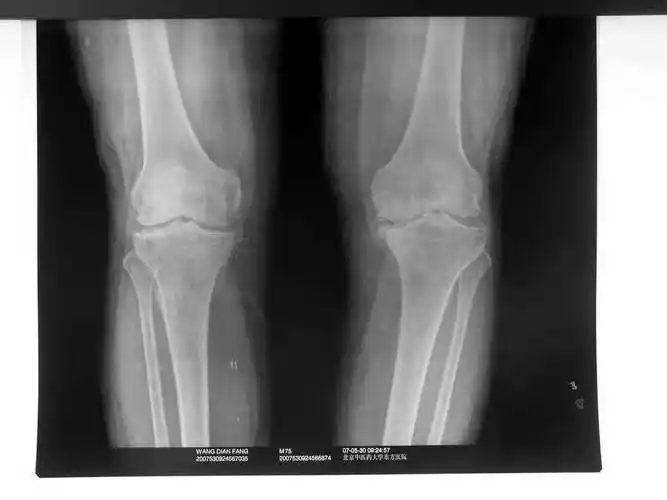

伸直就感觉里边硬邦邦的昨天在家附近医院拍的片子说考虑骨折,让做ct

各位高手请帮忙看下一张膝关节平片

dr和ct可以清晰地显示骨质的形态及结构,可以判断是否存在骨质疏松